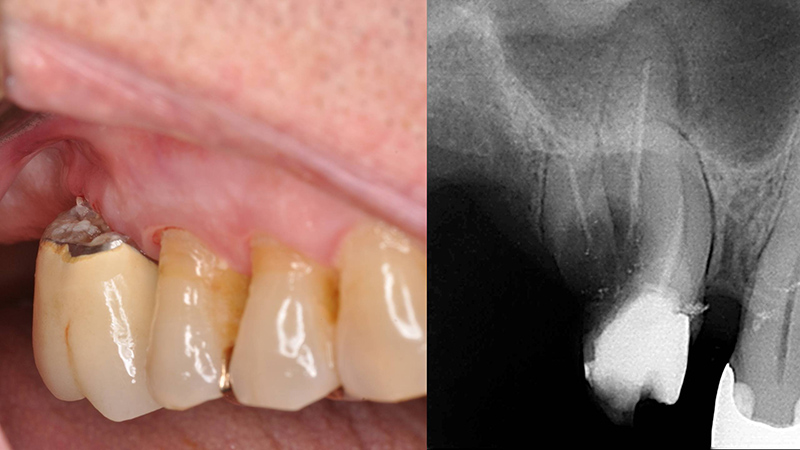

Patiente se présentant avec une récidive de carie sous une couronne.

Le patient doit cependant être averti que ce protocole peu invasif ne résoudra pas le problème du préjudice esthétique lié à la résorption osseuse.